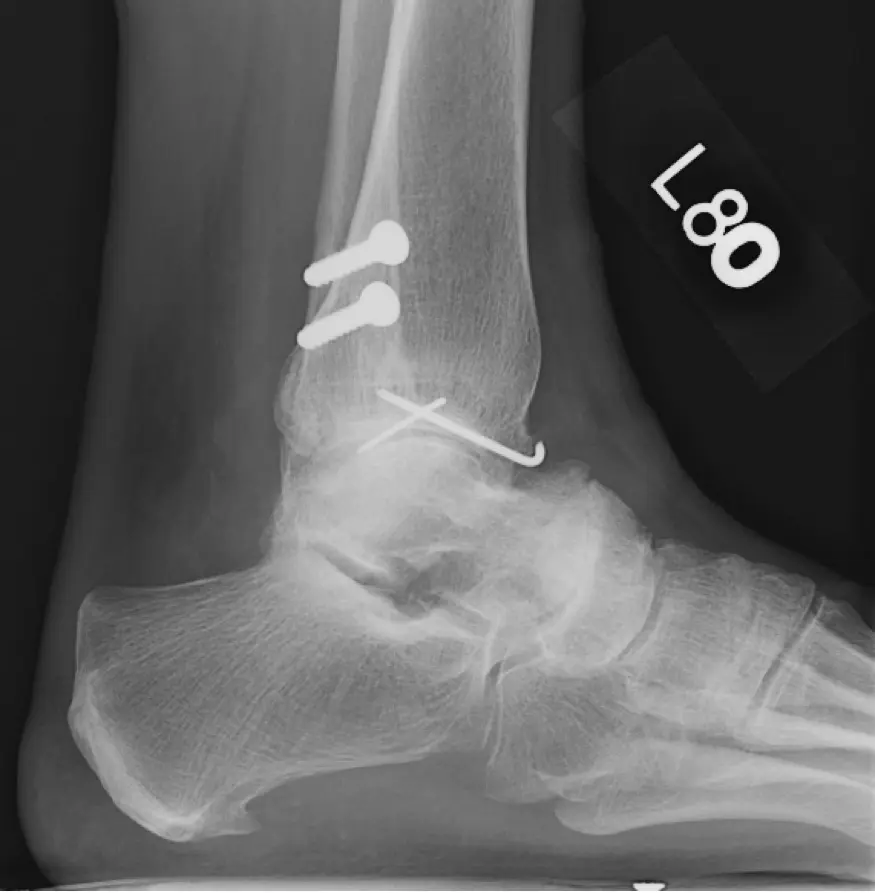

“I fractured my ankle in 1980 and had pins

and screws put in. I didn’t have any issues with it until about 2008 when I

started having pain in my ankle. I love to walk and the pain was preventing me

from walking as far as I used to,” says Hodges.

“Sharon came to see me in 2001. She had an X-ray and a physical exam. By watching her walk, I checked her alignment,” says Park. “In addition to ankle arthritis, she had some arthritis in the joint just under the ankle and in other joints of the foot as well.  This combination makes total ankle replacement a preferred option compared to ankle fusion for this specific patient.”